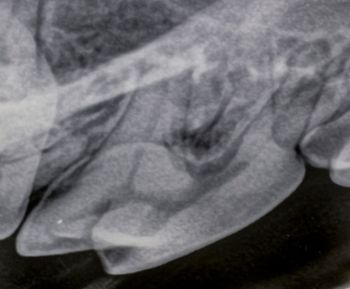

Intraoral radiography can help identify this pathology in your patients-and guide you toward the next step in your treatment plan.